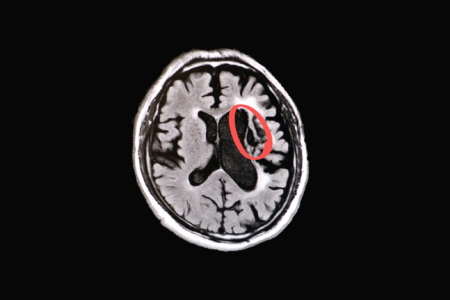

【大紀元2025年06月19日訊】(大紀元記者徐乃義台灣桃園報導)曾因急性腦中風就醫急診的患者,雖及時透過取栓手術搶通血管,術後卻留下右側肢體無力的後遺症,連穿衣、行走都需家屬協助。歷經傳統治療與復健仍未見明顯改善,經轉介聯新國際醫院功能與再生醫學中心盧炳昇醫師評估後,導入內生性幹細胞輔助療法,歷經一期6次約半年的時間,患者從需要家屬攙扶進步到能自主行走,生活品質明顯改善。